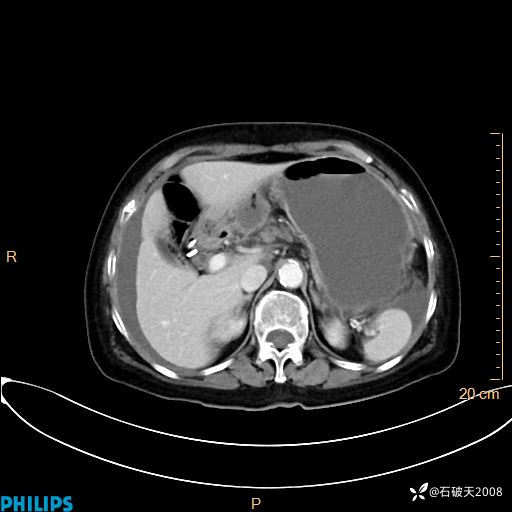

平扫